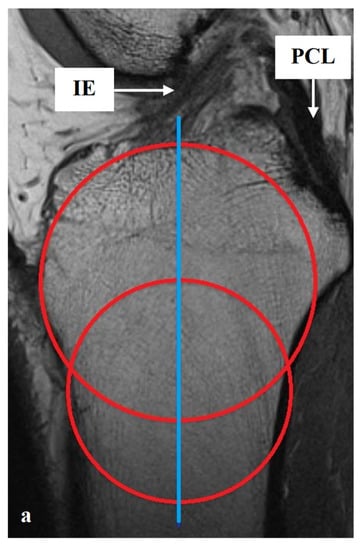

All measurements were taken via the PACS system (Picture Archiving and Communication System). Software from GE Healthcare called CentricityTM Universal Viewer was used (RA1000, edition 2019, Buckinghamshire, Great Britain). The osteoarthritis score of each knee joint was classified according to Kellgren/Lawrence (KL), in order to group patients as KJH or KJD. The TS was measured on the medial and lateral knee-joint surface according to Karimi et al. (TSKmed and TSKlat) [37] and Hudek et al. (TSHmed and TSHlat) [38]. As a reference for determining the inclination of the tibial plateau, Karimi et al. described the dorsal tibial bone cortex and Hudek et al. the tibial-shaft axis. Figure 1 and Figure 2 show the principle of the measurement methodology.

Figure 2.

Exemplary depiction of the measurements of the tibial slope according to Hudek et al. [38] for medial (TSHmed, (b)) and lateral (TSHlat, (c)) knee-joint surface: The measurements of TSH were performed in sagittal view of the knee joint in MRIs. To determine the right position of tibial-shaft axis for each TSHmed and TSHlat, a reference line was set in the best available image. To detect the tibial-shaft axis as accurate as possible, two virtual circle stencils were used (a). The reference structures were the posterior cruciate ligament (PCL) and the intercondyloid eminence (IE). Based on this reference line, the inclination angle of the tibial plateau was determined in the medial (TSHmed, (b)) and lateral (TSHlat, (c)) joint sections.